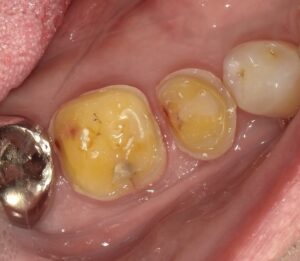

画像はオーバーレイ用に削った歯です。

歯の頭の部分は全面に削らないといけません。